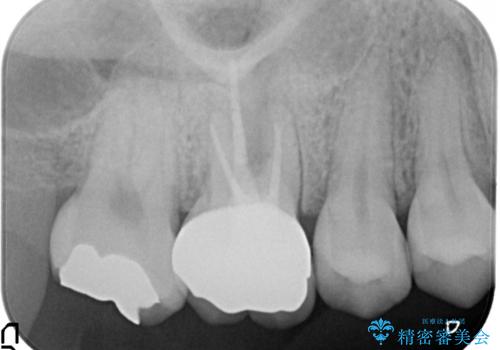

根の神経の治療を行い、セラミックを装着する計画としました。

根の神経が細菌に感染するとこのように、膿の出口ができることがあります。

その場合は、根の中の治療(根管治療)が必要になります。